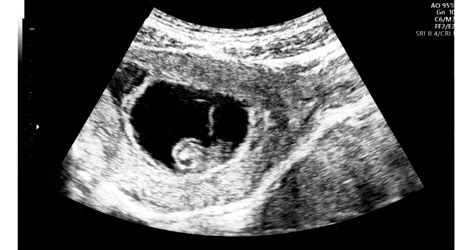

A gyermekáldásra váró párok számára kiemelten fontos a peteérés pontos idejének meghatározása. A follikulometria, vagyis a tüszőérés ultrahangos nyomon követése, egy egyszerű, fájdalommentes és megbízható vizsgálat, amely segít az ovuláció legvalószínűbb időpontjának megállapításában. A vizsgálat során a petefészkekben fejlődő tüszők méretét és számát, valamint a méhnyálkahártya állapotát vizsgálják hüvelyi ultrahang segítségével.